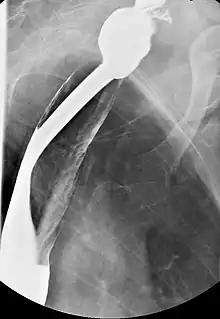

Serial contrasted gastrointestinal radiography or upper-gastrointestinal endoscopy may reveal the web in the esophagus. Blood tests demonstrate a hypochromic microcytic anemia that is consistent with an iron-deficiency anemia. Biopsy of involved mucosa typically reveals epithelial atrophy (shrinking) and varying amounts of submucosal chronic inflammation. Epithelial atypia or dysplasia may be present. It may also present as a post-cricoid malignancy which can be detected by loss of laryngeal crepitus. Laryngeal crepitus is found normally and is produced because the cricoid cartilage rubs against the vertebrae.

Imaging

Barium esophagography and videofluoroscopy will help to detect esophageal webs. Esophagogastroduodenoscopy will enable visual confirmation of esophageal webs. The webs occur due to sub-epithelial fibrosis.